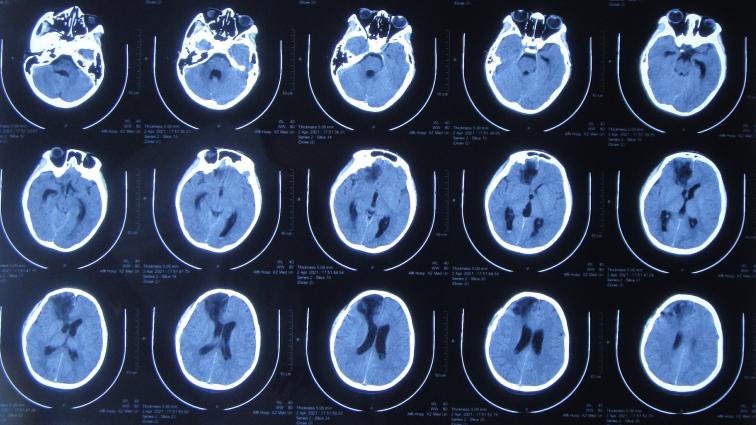

次日即2021年3月24日,转入该院的神经外科,仍发热体温高达38.0-39.0℃,查脑CT示出现水肿,仍有出血( 图-3 ),给予抗感染治疗。

图-3: 2021年3月24日脑CT